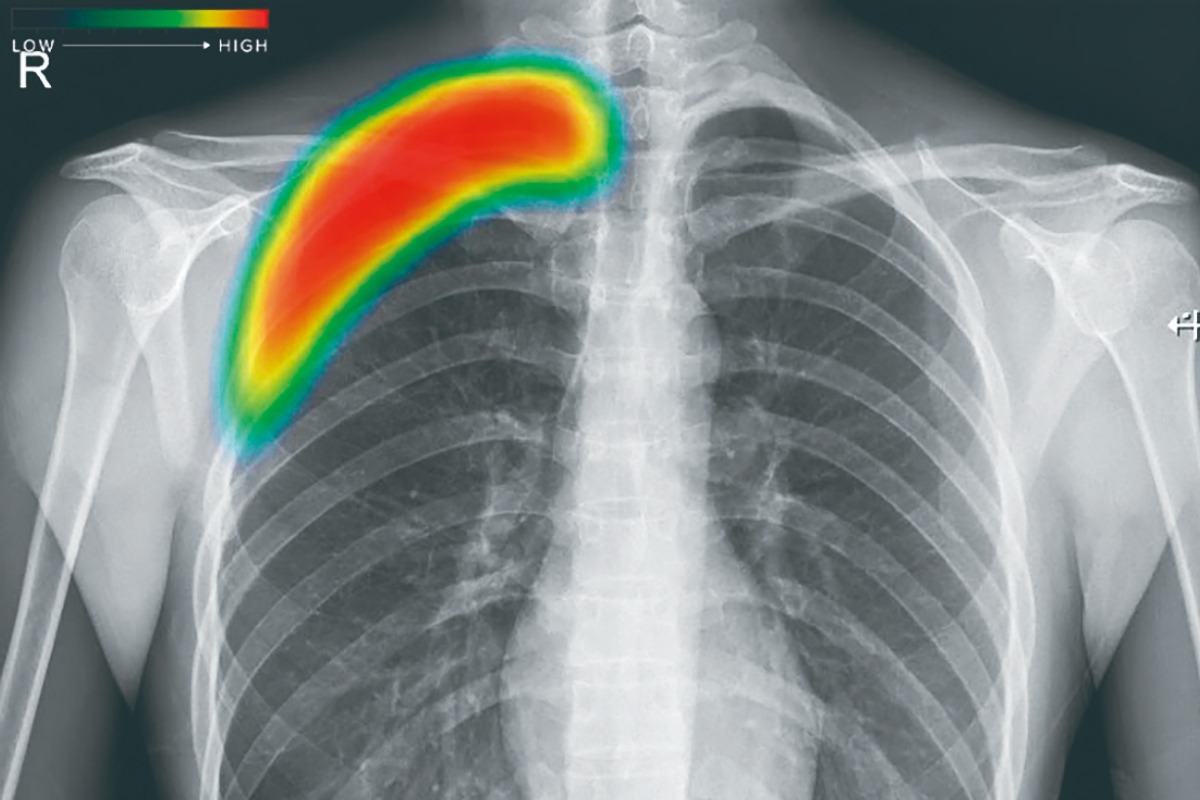

▲先進機器で鮮明に。日常診療を支える胸部レントゲン

同院では最近、レントゲン装置を先進機器へと更新。高画質化に加え、AIによる画像解析を併用することで、病変の見落としを防ぐ体制を整えた。撮影した画像はAIが自動でチェックし、疑わしい部位を色分け表示。最終的な判断は医師が行うが、異常の早期発見につながる大きな武器となっている。

▲AIが異常部位を色で示唆。見落とし防止に貢献

レントゲンは定期健診や不調時の基本検査として多くの患者が利用するだけに、こうした進化は安心感にも直結する。見慣れた検査の裏で進化を続ける設備。その先には、地域の人々がより長く健康に暮らせる未来を見据えたクリニックの姿勢がある。